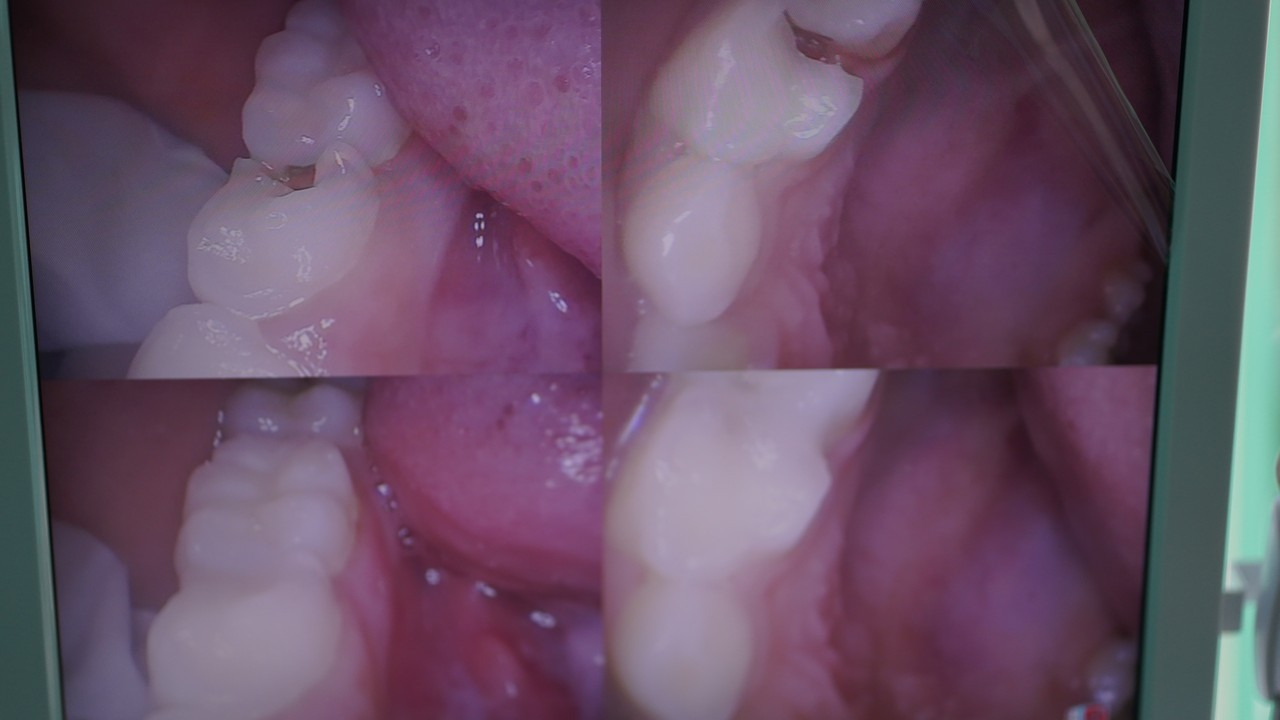

Orang tua juga diharapkan memantau dan menjaga kebersihan gigi susu. Meskipun bersifat sementara, tapi ternyata gigi susu berperan aktif sebagai penunjuk arah tumbuhnya gigi permanen. Oleh karena itu, jangan sampai gigi tersebut rusak atau keropos.